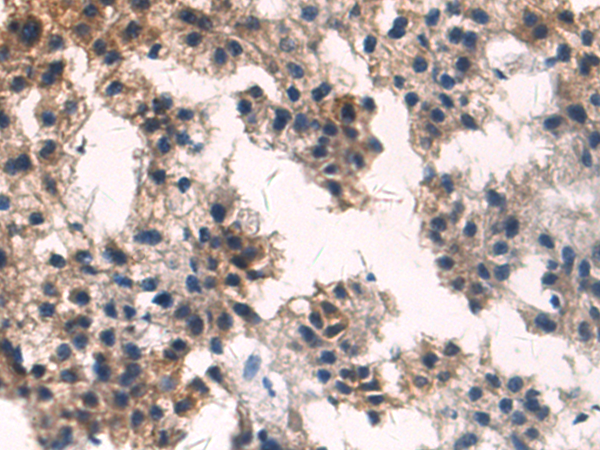

分类: 科研抗体货号: P13823别名: FBP; FOLR; NCFTD; FRalpha应用: WB,IHC反应种属: Human, Mouse